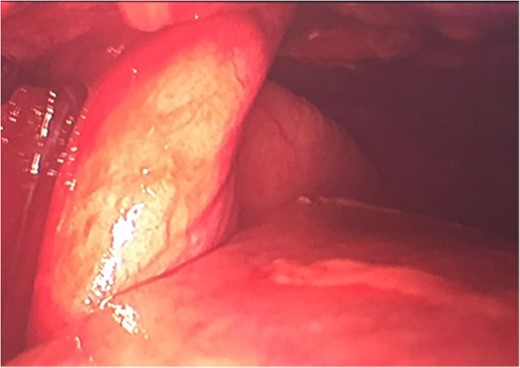

A lingular lung segment protruding through the fifth ICS was observed (Fig. 2), as well as a moderate hemothorax. Lung tissue reduction was performed.

Due to the macroscopic appearance of ischemia and venous congestion of the involved lung tissue, a non-anatomic lingular resection using 60 mm Echelon Flex Stappler® was performed (Fig. 3) as well as a chest washout.

Wedge resection of ischemic lung through chest wall herniation.